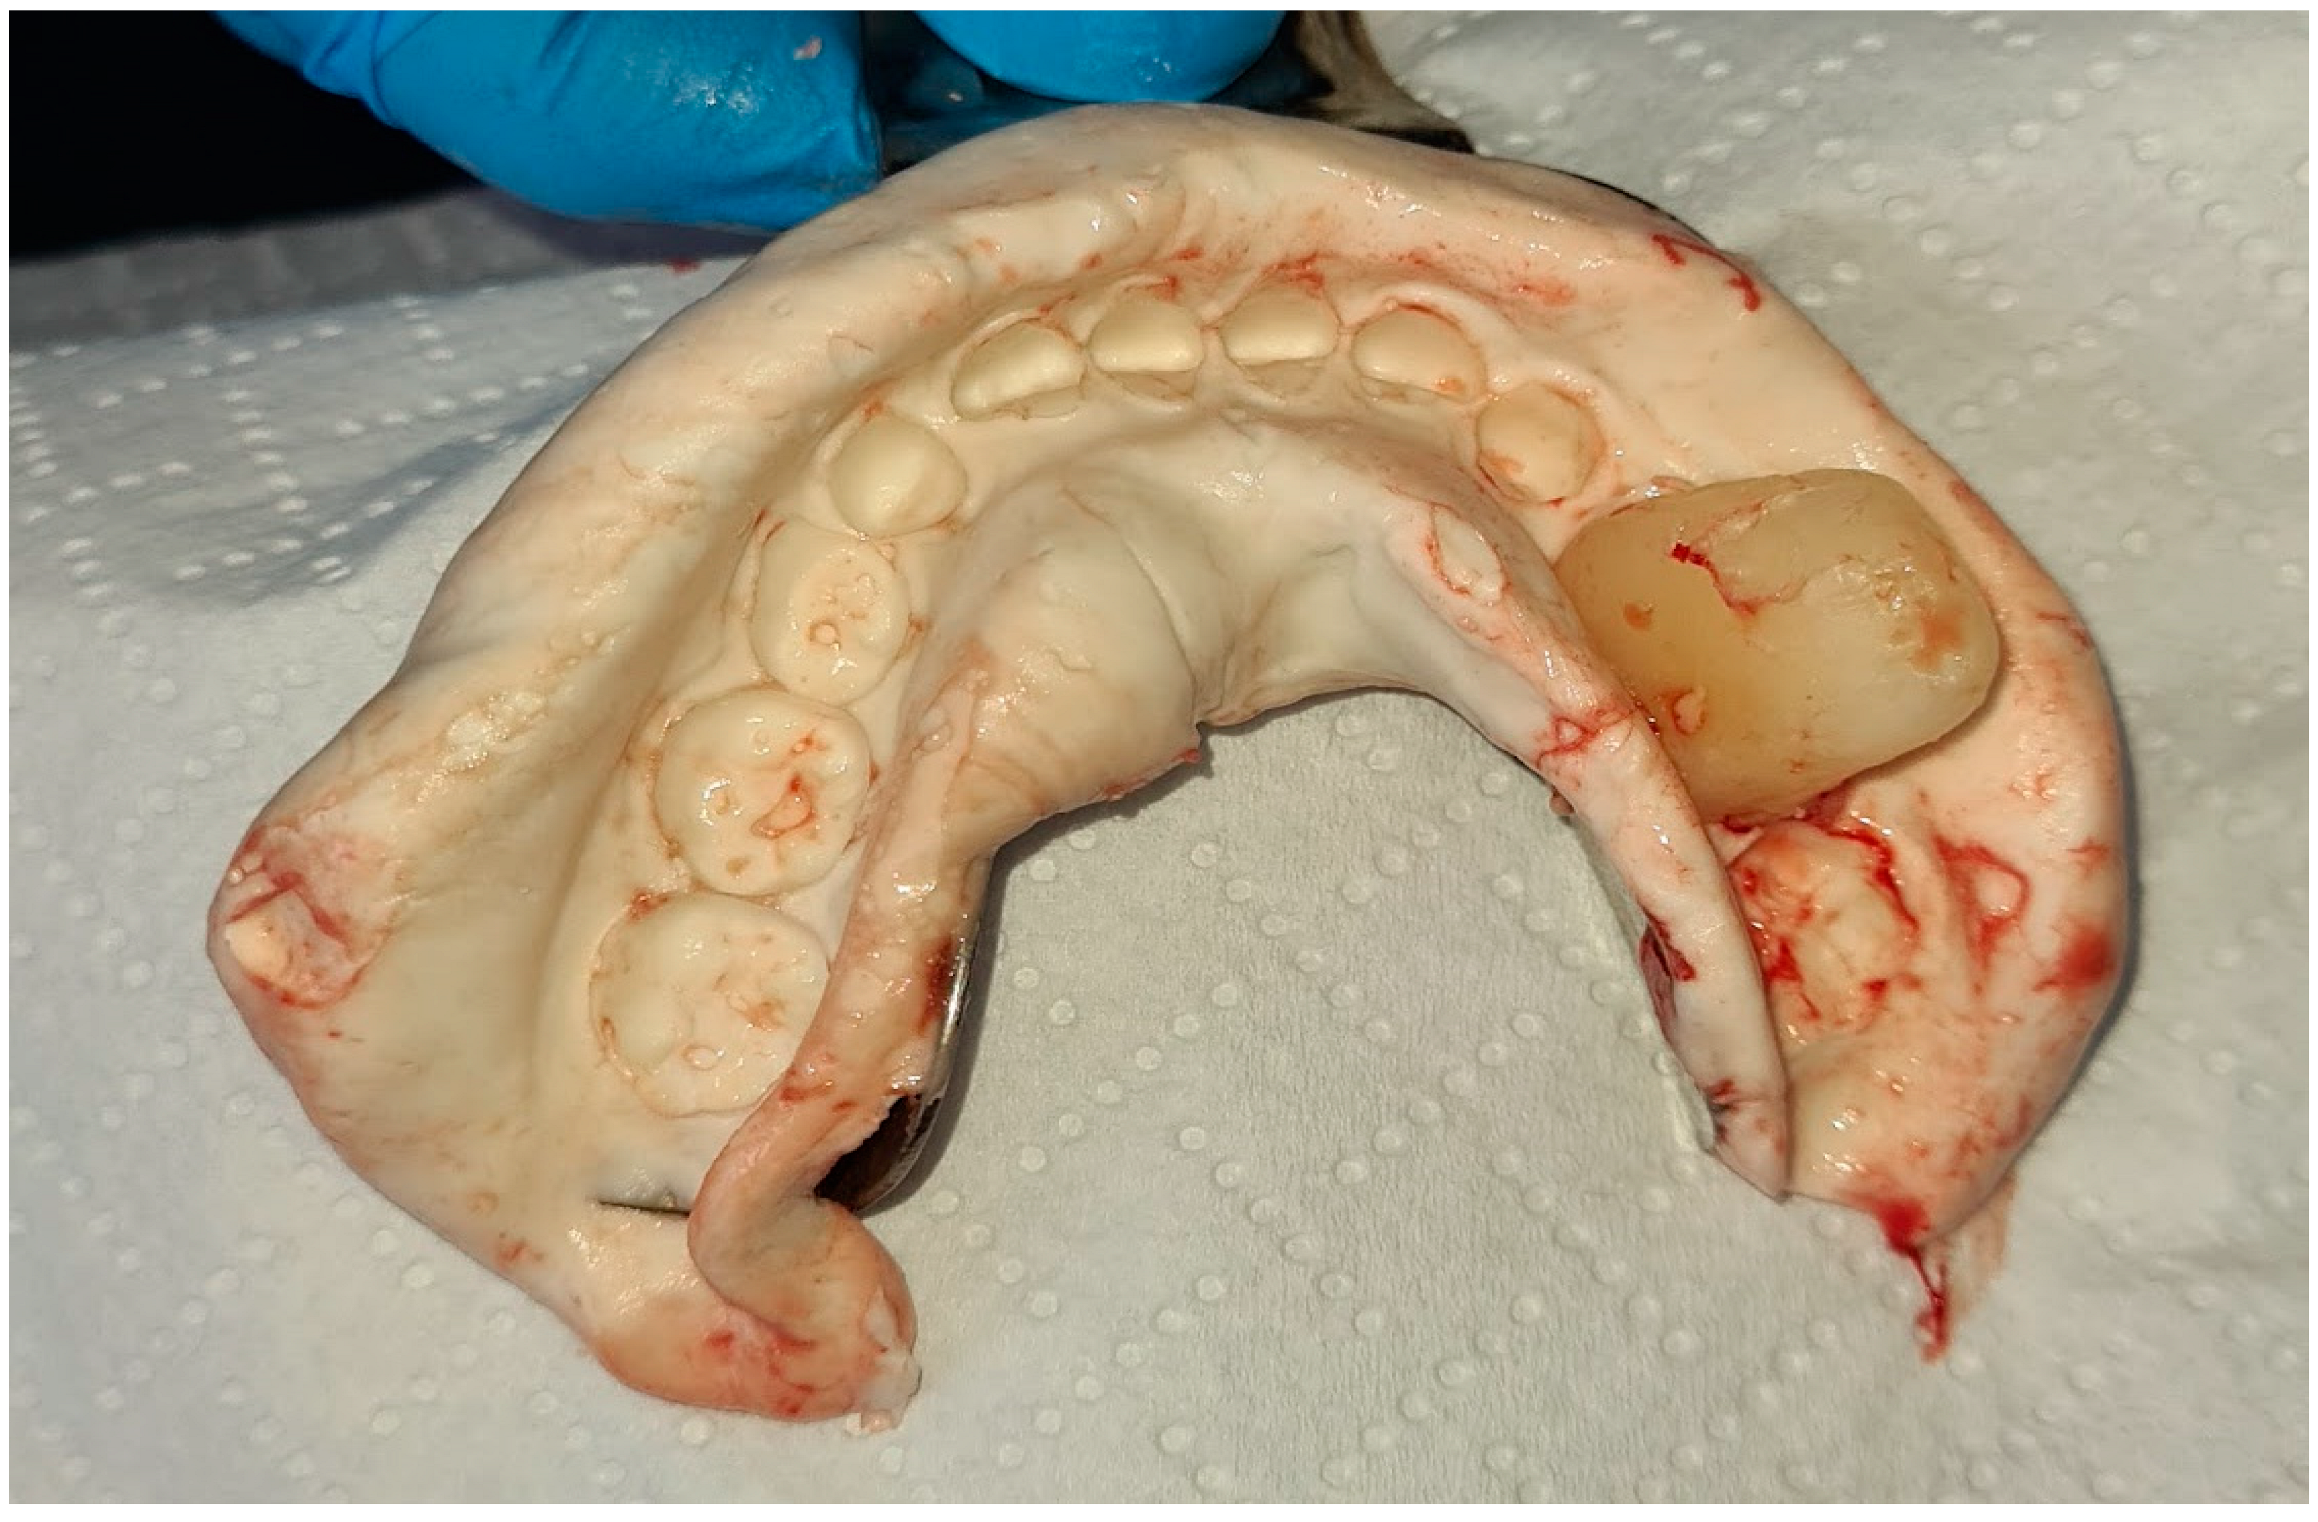

2. Case Report